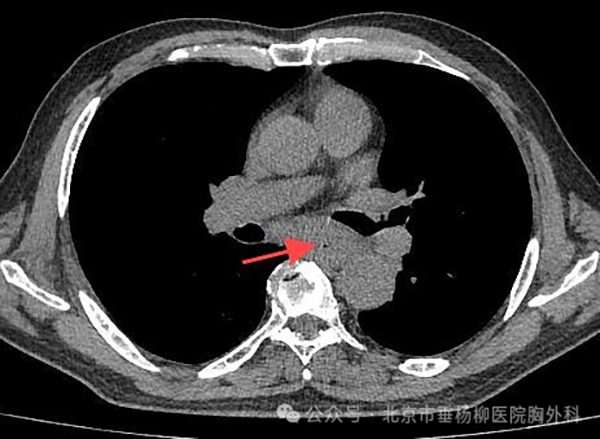

图1

患者,老年男性,主因“进行性吞咽困难3月”入院,入院后胸部CT可见食管中下段管壁增厚,官腔狭窄(图1)。完善胃镜检查提示食管距门齿约23-30cm占位性病变(图2),胃镜下给予留置经鼻空肠营养管置入,给予肠内营养灌注,活检病理提示食管高-中分化鳞状细胞癌,给予其化疗联合免疫治疗一周期后出院,出院后鼻饲饮食。